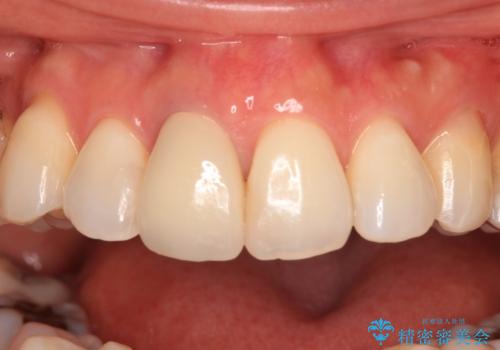

失活により変色した前歯 オールセラミッククラウンによる審美歯科治療

- 前歯の変色を気にして来院された患者様です。

ラミネートベニアによる治療を以前受けていたものの、神経組織が失活して以降、徐々に変色してきたとのことでした。

オールセラミッククラウンにて補綴治療を行うこととしました。

周りの歯と調和した、自然な仕上がりとなりました。